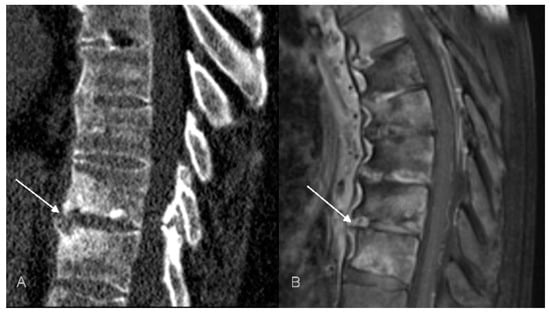

Interestingly, in three patients we have observed the features of pseudoarthrosis in an ankylosed spine (unstable Anderson lesion), a finding that to the best of our knowledge has not yet been reported in patients with CNO/SAPHO syndrome. All pseudoarthroses occurred in the thoracic region and, in one patient, pseudoarthrosis was associated with an aggravation of pain (Figure 6). This observation suggests that in patients with a longstanding CNO and the worsening of symptoms the radiologist should look for a developing pseudoarthrosis, just like in patients with a longstanding AS or with DISH [66].

Figure 6.

Unstable Anderson lesion in a 65-year-old patient with SAPHO syndrome. Sagittal CT reformat (A) and MRI (B) shows interruption of syndesmophytes and disc space widening (arrows).